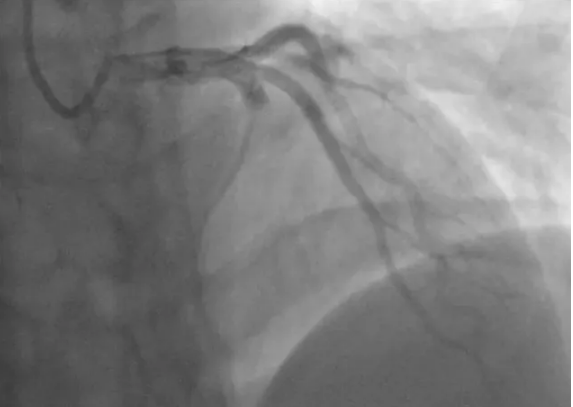

我曾診治過一位年輕的男性患者小蒲,只有21歲。小蒲術(shù)前的冠脈造影顯示 前降支血管嚴(yán)重堵塞。我當(dāng)時(shí)正在查房,接到急診科電話趕忙來會(huì)診。看到小蒲的第一份心電圖,我遲疑了一會(huì),畢竟年輕啊,才21歲。

反復(fù)向家屬解釋后,小蒲最終被緊急推入了介入導(dǎo)管室。進(jìn)行緊急冠脈造影,造影結(jié)果顯示,原本應(yīng)該粗大明顯的冠脈血管前降支的顯影只剩下1厘米左右。

前降支被堵死了!前降支又被叫做生命支,承擔(dān)著左心室的供血功能,這根血管被堵,意味著生命線被堵。

馬上我們就下導(dǎo)管、導(dǎo)絲、球囊擴(kuò)張。按理球囊過去了,血流就應(yīng)該恢復(fù),但造影顯示血流恢復(fù)并不通暢,原來大量的血栓造成堵塞,又用導(dǎo)管反復(fù)抽吸血栓。

就在血流恢復(fù)、準(zhǔn)備結(jié)束手術(shù)時(shí),造影卻顯示前降支血流速度又慢了下來,當(dāng)機(jī)立斷,必須上支架!術(shù)后,小蒲的冠脈血流恢復(fù)情況良好。